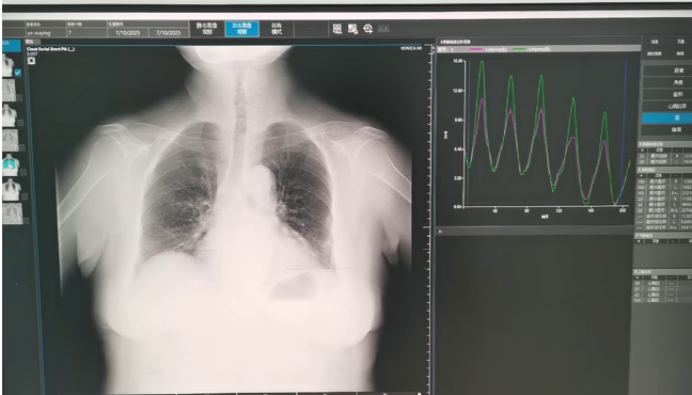

• 动态胸片下横膈垂直位移图表:平静呼吸时间,两侧膈肌运动曲线平滑,对称,未见锯齿样改变(图3);深呼吸时双侧膈肌活动度严重受限,并伴有锯齿状运动模式(图4)。由此得出结论:患者呼吸运动配合欠佳,双侧膈肌平静呼吸、尽力呼吸位差均小于30 mm,考虑双侧膈肌功能障碍。

图片

3  平静呼吸时膈肌垂直位移图

4  深呼吸时膈肌垂直位移图

7月14日,动态胸片示双侧膈肌移动度正常。平静呼吸时,右侧膈肌移动度为12.0 mm,左侧为16.0 mm(图8);尽力呼吸时,右侧膈肌移动度为48.0 mm,左侧为50.0 mm(图9)

6)动态胸片: 实时连续拍摄运动中的胸部图像, 识别矛盾的膈膜运动, 适用于诊断膈肌功能障碍, 结果与标准透视或超声检查结果一致

目前动态胸片诊断膈肌功能减弱、膈肌功能障碍,仍缺乏共识标准。以下为我院目前参考的动态胸片下膈肌功能正常的参考标准:①观察平静呼吸、尽力呼吸时,两侧膈肌位移曲线是否平滑、相近、对称,是否有锯齿状抖动、矛盾运动。②根据测量表量化两侧膈肌移动度。平静呼吸移动度为10~20 mm,尽力呼吸时移动度>40 mm,尽力呼吸相对平静呼吸增加>30 mm;平静呼吸、尽力呼吸时两侧膈肌移动度差值<10 mm。